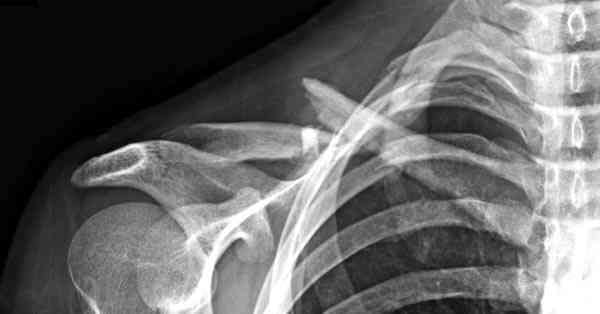

Второй случай тоже недавно оперирован по поводу

ложного сустава, в марте травма, через 4.5 половиной

операция..

Описанный случай это больная моего партнера, мы недавно случай разбирали на нашей конференции (Morbidity and Mortality Conference аналог клинического разбора)

Выставлен как пример, к чему может привести

неудачно выбранный фиксатор.